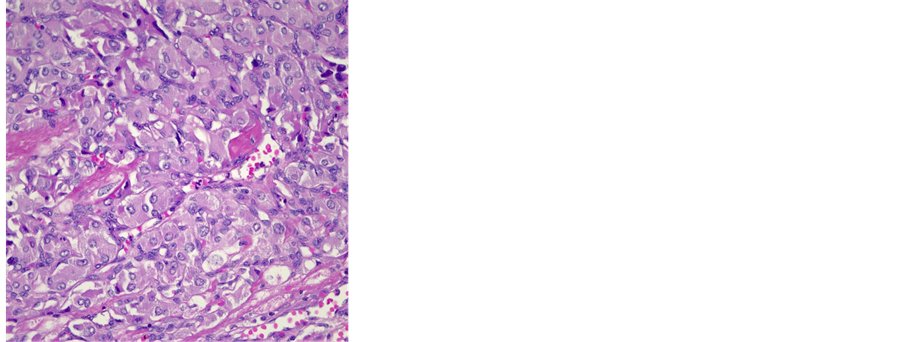

Histopathologically, the gross specimen consisted of a round to ovoid encapsulated mass of 6.4 cm in diameter, with a predominantly homogeneous, focally fibrotic cut surface. Light microscopy showed a solid neoplasm composed of a monomorphous population of round to polygonal cells with amphophilic, finely granular cytoplasm. The lesion’s architecture displayed a conspicuous nested (“Zellballen”) pattern throughout (Figure 3(a), Figure 3(b)). Mitotic activity was virtually absent, and neither extracapsular vascular invasion nor necrosis was noted. Nevertheless, focal encroachment upon the adjacent left atrial musculature was noted at the tumor’s periphery (Figure 3(c)). Immunohistochemistry confirmed expression of the neuroendocrine markers chromogranin A and synaptophysin, while the Zellballen architecture was highlighted by staining for S100 protein in sustentacular cells. Of note, tumor cells exhibited intense staining for SDHB (Figure 3(c)).

Based on these findings, the pathological diagnosis of paraganglioma with focal infiltration of the left atrium was issued.

Figure 3. (a) Histological features of a paraganglioma. Note the organoid architecture (“zellballen”) arranged around ectatic, sinusoidal blood vessels. The cubic to polygonal tumor cells presents a partially amphophile, partially eosinophilic cytoplasm, moderate anisokaryosis and no mitotic activity (HE × 10); (b) Focal invasion of the left atrium. Several areas were noted, where single cardiac myocytes were surrounded by tumor cells, hence a focal invasion of the heart was postulated (HE × 40); (c) Immunohistochemical reaction with SDHB: 100% of the tumor cells presented a strong cytoplasmatic reaction (×10).